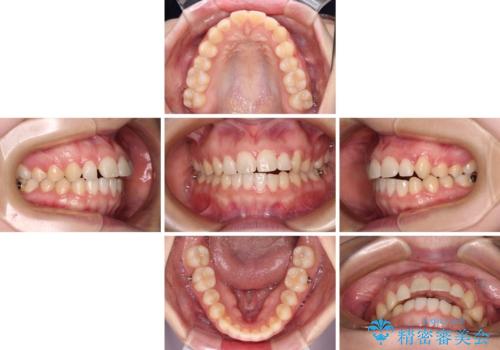

- 八重歯を気にして来院された患者様です。

八重歯のために乳歯が残存していたため、乳歯を抜去して八重歯となっている犬歯を歯列に収めることとしました。

八重歯の移動量が多くなるため、インビザラインと併用してワイヤー矯正を行い、八重歯を改善した後に、上下歯列をインビザラインで整えることとしました。

犬歯は歯根が長くて太いため移動に時間がかかる上に、周囲の歯が八重歯に寄ってきてしまうため、仕上がるまでに期間がかかりました。